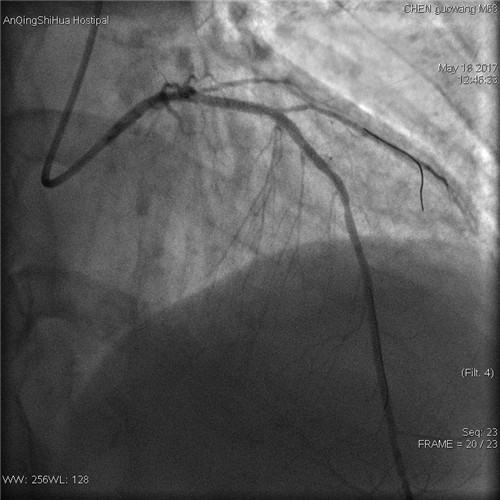

術(shù)后 回旋支血流通暢

術(shù)者先用普通預(yù)擴(kuò)張球囊預(yù)處理病變,后以與支架匹配的切割球囊于病變處擴(kuò)張,在對(duì)病變血管充分預(yù)處理后,再用藥物球囊持續(xù)擴(kuò)張。復(fù)查造影顯示,殘余狹窄<20%,血流通暢,未見明顯的夾層、慢血流等并發(fā)癥,“介入不植入”藥物球囊治療大獲成功。